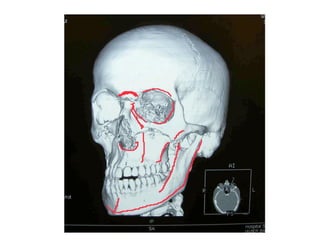

Este documento describe los principios de construcción de la arquitectura craneofacial, incluyendo el metamerismo, la simetría y la paquimería. Explica la organización peri-cavitaria del cráneo a través de columnas y vigas, y analiza las diferentes fascias profundas del cuello. También destaca la importancia de conocer la irrigación ósea con orientación quirúrgica, mencionando los principales aportes vasculares y suplementarios así como el origen, trayecto y retorno venoso de la carót